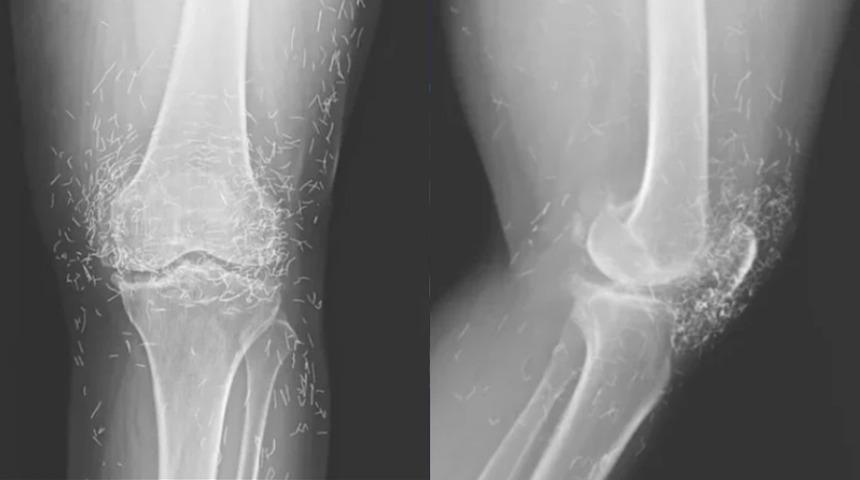

Güney Kore’de 65 yaşındaki bir kadın, şiddetli diz ağrısı şikâyetiyle hastaneye başvurdu. Yapılan röntgende yüzlerce altın iplik ile birlikte kemiklerde sertleşme, kalınlaşma ve mahmuz benzeri çıkıntılar tespit edildi.

Kadının daha önce kireçlenme (osteoartrit) tanısı aldığı, ancak ağrı kesici ve steroid tedavilerinden sonuç alamadığı öğrenildi. Mide rahatsızlığı nedeniyle ilaçları bırakan kadın, haftada birkaç kez “altın iplik akupunkturu” seanslarına katılmaya başladı.

Bu yöntemde, kısa ve steril altın iplikler deri altına yerleştirilerek sürekli uyarım amaçlanıyor. Doktorlar, ipliklerin vücutta bilinçli olarak bırakıldığını ancak zamanla yer değiştirebileceğini, kist oluşumu ve enfeksiyon gibi riskler taşıdığını belirtiyor.

Altın iplik akupunkturu, Asya’da kireçlenme ve iltihaplı romatizma tedavisinde yaygın kullanılıyor. Ancak uzmanlar, bu yöntemin etkinliğini destekleyen yeterli bilimsel kanıt olmadığını vurguluyor. Ayrıca bazı hastaların bu tedavi nedeniyle gerekli tıbbi müdahaleleri geciktirdiği uyarısı yapılıyor.

Daha önceki vakalarda, altın ipliklerin vücutta hareket ederek başka bölgelere ulaştığı ve enfeksiyona neden olduğu bildirildi. Ayrıca iplikler, röntgen ve MR gibi görüntüleme yöntemlerini zorlaştırabiliyor, hatta damar hasarına yol açma riski taşıyor.